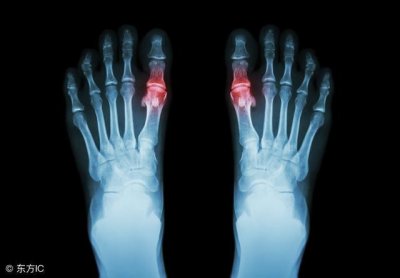

2、血管疾病

假如皮肤上莫名其妙的出现了一些小红点,而且有凸起的表现,过了一个月甚至更长的时间都没有消失,要警惕是不是血小板或者血管出现了健康问题。

尤其是樱桃状血管瘤发生时,患者的皮肤上就会出现密密麻麻,色泽鲜艳的小红点。

假如短时间内没有发展的话,不用过多的担心,但如若没过多久樱桃状血管瘤就有了扩大的表现,还需要进一步去医院检查。